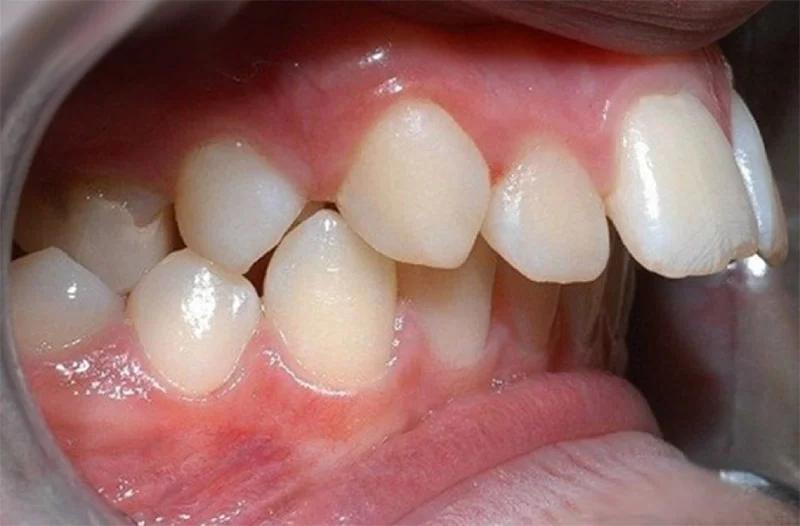

Dạng 1: Hô do răng

Trong trường hợp hô hàm trên do răng, vấn đề không phải do xương hàm. Nó chủ yếu xuất phát từ việc trục răng bị nghiêng quá mức. Từ đó khiến các răng cửa nhô ra phía trước. Đây là dạng hô phổ biến mà răng có xu hướng mọc không đúng vị trí. Theo thời gian nó tạo nên sự lệch lạc trong khuôn miệng.

- Chỉ răng hàm trên bị chìa ra phía trước. Còn hàm dưới vẫn giữ vị trí bình thường.